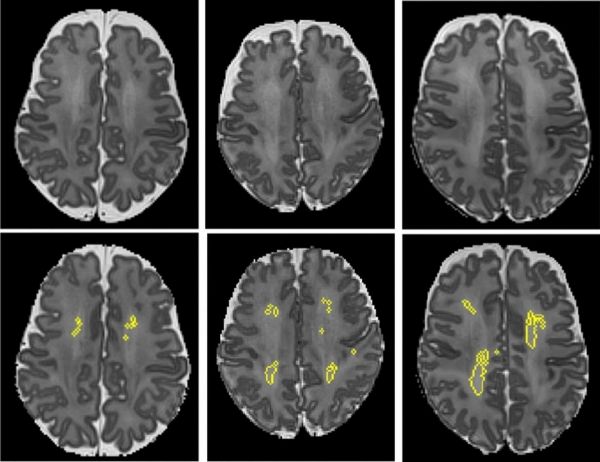

Image: These MRI scans show diffuse white matter abnormality (DWMA). The top three panels display raw MRI images from very preterm infants born at 27 weeks (left), 26 weeks (center) and 31 weeks (right) gestation. Higher signal intensity can be seen in the central white matter, particularly for the 31-week gestation infant. The bottom panels display the corresponding slices with objectively segmented DWMA in yellow. The 27-week infant (left) was diagnosed with mild DWMA, the 26-week infant (center) was diagnosed with moderate DWMA, and the 31-week infant had severe DWMA. (Credit: Cincinnati Children's and Nature Scientific Reports)